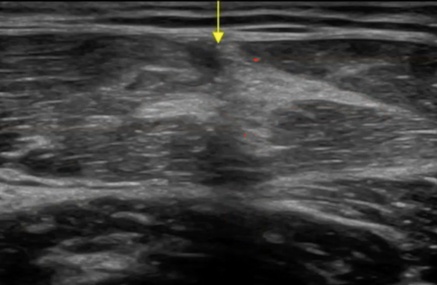

El recto anterior tiene un septo central en forma de S (azul). Las roturas musculares del recto anterior, son frecuentes próximas al septo (aunque tambión podemos encontrarnos roturas miofasciales que tambien te enseñaremos).

El contorno de la sección transversal del recto anterior queda delimitada por el contorno (verde).